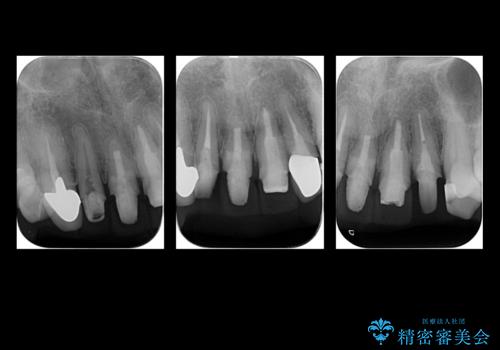

- 他の部位の治療で来院されていましたが、30年以上前に行った前歯のかぶせ物のきわがあっておらず虫歯になってきていました。

神経の治療から念のためやり直ししてからセラミックでかぶせました。

金属の土台が入っていましたがすべて外し、ファイバーコアでやり替えています。

- 101.2万円(ジルコニアクラウン12.1万円×4 仮歯1.1万円×4 ファイバーコア2.2万円×4 精密根管治療9.9万円×4)費用は治療当時の料金となります